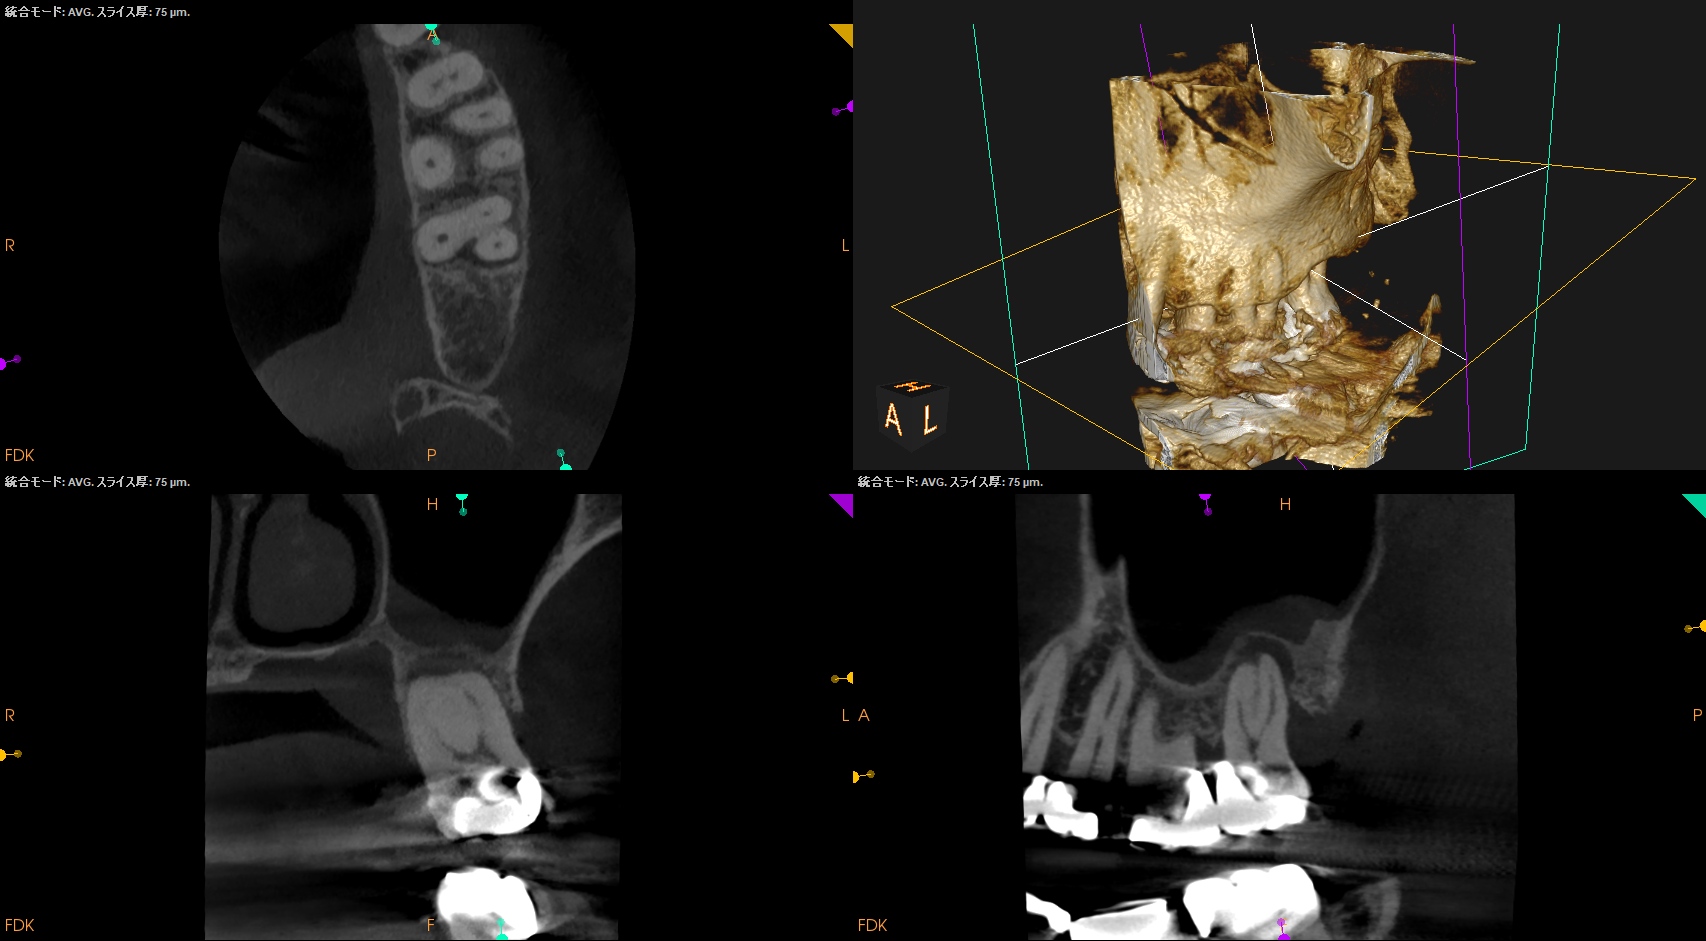

#15 RCT(2024.7.31)

術後にPA, CBCTを撮影した。

MB

DB

P